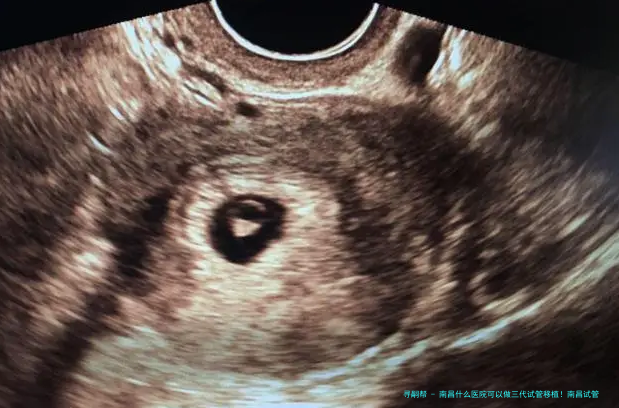

三代试管移植技术是辅助生殖技术中的先进手段,主要用于解决精子健康状况差、卵子质量问题以及遗传性疾病等方面的生育难题。 通过严格的胚胎检查筛选和遗传检测,可以提高成功率,同时减少因遗传不足导致的子孙健康风险。 三代试管移植技术的使用为许许多多家庭提供了生育希望。

1. 宫颈扩张: 医生会使用仪器将子宫颈扩张,以便胚胎顺利进入子宫腔内。2. 胚胎移植: 将选择好的胚胎通过细长管导入子宫内。整个过程只需几分钟时间。3. 观察和监测: 移植后,需要定期进行孕激素水平监测,确保胚胎着床成功。